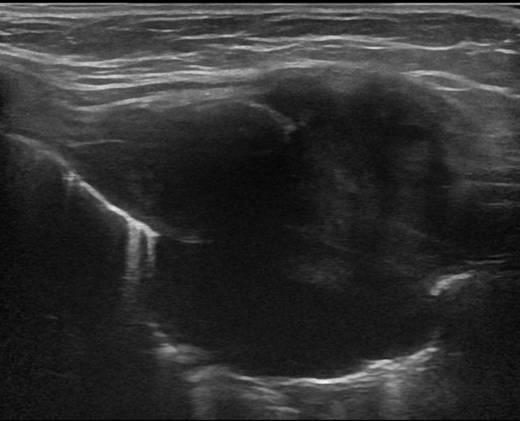

Di căn thành ngực - Ảnh 4

Di căn thành ngực

» Thông tin: Nam giới – 64 tuổi.

» Lâm sàng: Khối thành ngực / K vòm.